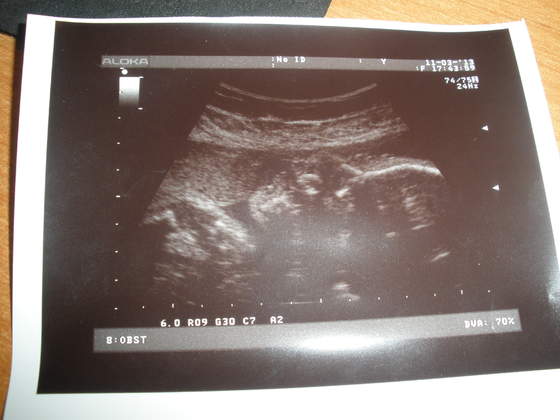

Na tym etapie ciąży trudno już o wyraźne zdjęcie ;-)